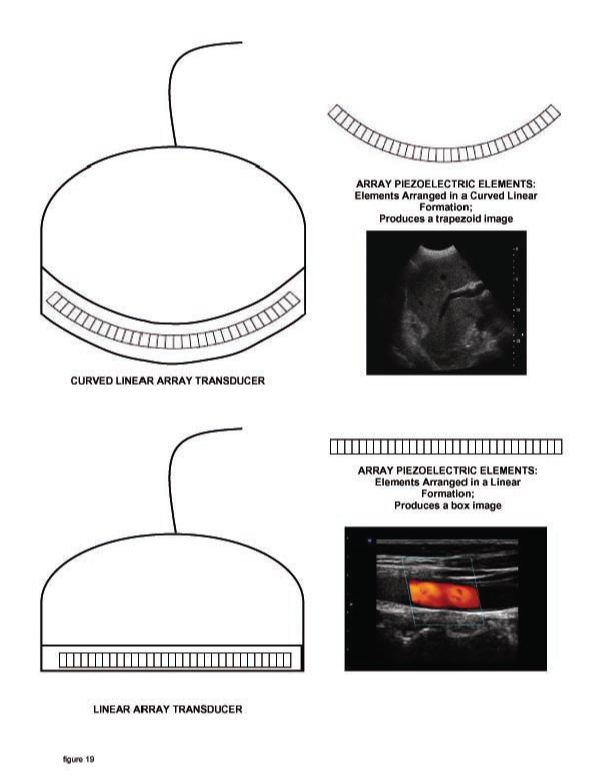

Linear transducer arrays. The top shows a curved linear array and its image format. The bottom shows an ordinary (straight) linear array and its image format, which is rectangular. Within the rectangle is a parallelogram-shaped inset commonly used for color flow or Doppler imaging. Note that phased arrays look physically like linear arrays but scan in an angle from a central point in the array and have a sector-shaped format exemplified by Figures 21 and 29.